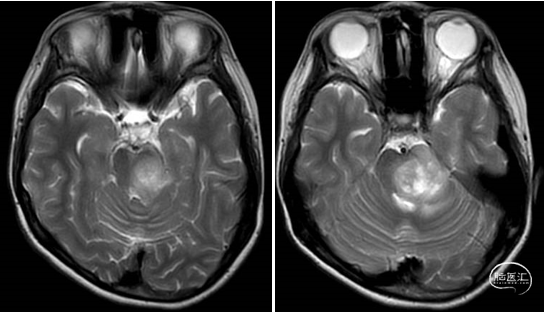

术前MRI

2023年9月13日 MRI T2

2023年9月13日 MRI+C

术后MRI